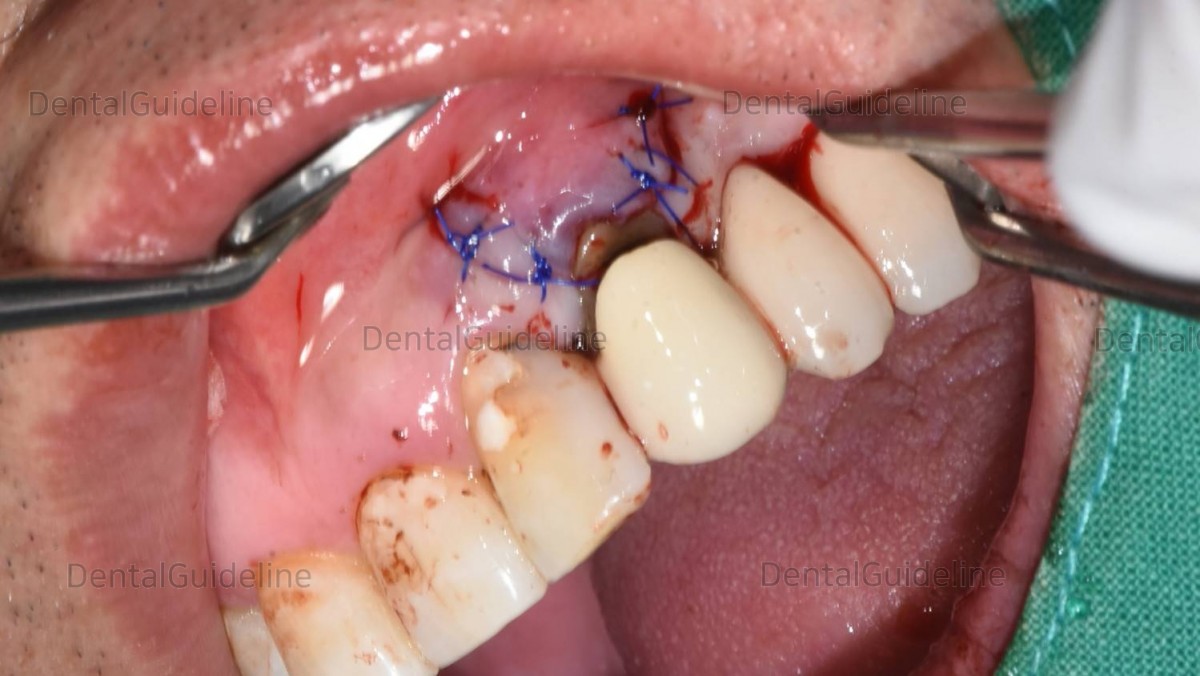

suture.